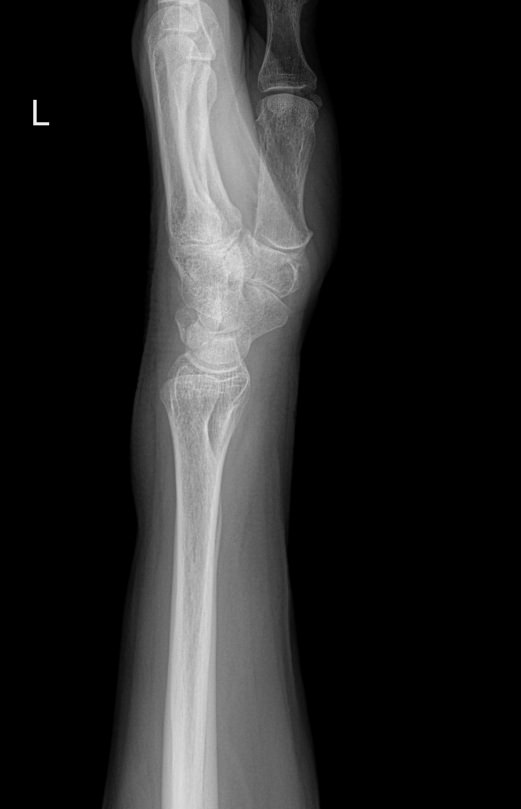

Самым первым исследованием запястья, наряду с лабораторными анализами, обычно является рентген. Это распространенный, простой в проведении и быстрый в получении результатов, а также высоко информативный для всей костной системы метод. В настоящее время он стал и практически безопасным в плане облучения: количество испускаемых лучей минимально и позволяет выполнять рентгенодиагностику несколько раз в год, не набирая при этом максимально допустимой дозы.

Что показывает рентген лучезапястного сустава

• Взаимоотношения суставных поверхностей ― в норме или вывих;

• Состояние суставной щели ― в норме, сужена, есть ли выпот и обызвествление капсулы;

• Состояние суставных поверхностей ― эрозии или ровный контур;

• Структура костной ткани ― типична, остеопения, деструкция или другие патологии;

• Переломы, трещины, костные обломки;

• Изменения в мягких тканях;

• Новообразования.

О других проекциях ― боковой, косых и специальных для исследования отдельных костей ― лечащий врач дополнительно пишет в направлении.